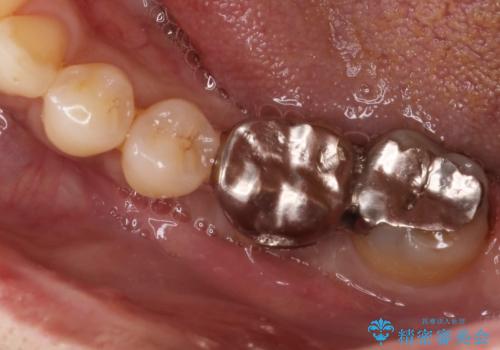

- Ⅲ度の分岐部病変をきたした第1大臼歯を抜去、待時しインプラントによる咬合回復を計画した。

インプラントの種類:strauman SLActive

かぶせ物の種類:Bellezza screw retain